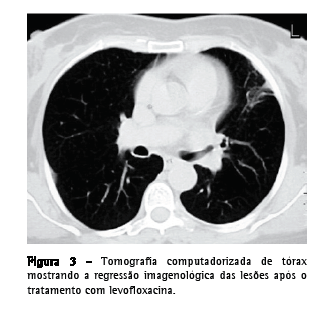

Uma paciente do sexo feminino, 55 anos de idade, caucasiana, não fumante, secretária, procurou atendimento no serviço de emergência. Tinha história de hepatite B crônica, hipertensão arterial, dislipidemia mista e múltiplas cáries dentárias não tratadas. Relatou que há três semanas havia iniciado quadro de dejeções diarréicas diárias, azia, desconforto retroesternal agravado pelo decúbito dorsal, astenia, anorexia e emagrecimento (5 kg). Uma semana depois haviam surgido toracalgia esquerda de características pleuríticas com agravamento progressivo, acessos freqüentes de tosse seca ao esforço e pico febril isolado. O eletrocardiograma foi normal, e a endoscopia digestiva alta revelou um cárdia complacente e gastrite antral. A telerradiografia de tórax mostrou hipotransparência heterogênea, esboçando perda de substância em seu seio, no terço médio do campo pulmonar esquerdo. A tomografia computadorizada de tórax evidenciou a presença de uma massa de 4 cm com conteúdo heterogêneo e continuidade pleural ao nível da língula e a presença de dois micronódulos subpleurais na região posterior do campo pulmonar direito (Figura 1). Procedeu-se ao estudo etiológico considerando-se a hipótese diagnóstica de neoplasia pulmonar como a mais provável. Do estudo analítico, salientam-se os seguintes resultados: velocidade de hemossedimentação = 98 mm/1a h; antígeno do câncer 125 = 63,3 U.mL-1 (<35,0); antígeno carcinoembriogênico = 3,55 ng.mL-1 (<2,5) e discreta elevação da proteína C reativa. O estudo imunológico sérico, os marcadores virais e o estudo analítico final não revelaram outras alterações relevantes. Os resultados da colonoscopia, da ultrassonografia abdominopélvica, da mamografia e da citologia cérvico-vaginal foram normais. A primeira fibrobroncoscopia realizada mostrou sinais inflamatórios difusos ao nível da língula. Os resultados do exame citológico de aspirado, lavado brônquico e lavado broncoalveolar foram negativos para células neoplásicas. O exame microbiológico em aerobiose foi também negativo, assim como a pesquisa de bacilos álcool-ácido resistentes. A paciente foi então submetida à biópsia aspirativa transtorácica (BAT), que, ao exame citológico extemporâneo, mostrou um processo inflamatório com supuração. Face a este resultado provisório, iniciou-se a antibioticoterapia com levofloxacina 500 mg via oral ao dia, e decidiu-se realizar uma segunda fibrobroncoscopia. Entretanto, o exame citológico da BAT revelou aspectos morfológicos compatíveis com a presença de Actinomyces, confirmada pelo exame microbiológico cultural do lavado brônquico e broncoalveolar da segunda fibrobroncoscopia, no qual se identificou A. naeslundii (Figura 2). A pesquisa de bacilos álcool-ácido resistentes foi negativa. Dada a melhoria clínica e radiológica após um mês de tratamento (Figura 3), optou-se por manter a antibioticoterapia já iniciada, cuja posologia foi alterada: levofloxacina 500 mg endovenoso ao dia por quatro semanas e, depois, 500 mg po qd. Não se verificou iatrogenia à terapêutica, a qual foi mantida por 16 semanas, até a completa normalização radiológica. Analiticamente constatou-se uma redução da velocidade de hemossedimentação e uma redução de ambos os marcadores tumorais inicialmente alterados, assim como a normalização da proteína C reativa. A paciente foi também submetida a tratamento dentário.

Habitualmente a lesão inicial apresenta-se como uma consolidação bem localizada que pode evoluir para a cavitação em metade dos casos, geralmente de pequenas dimensões. O derrame pleural é comum.(2) A infecção pode afetar múltiplos lobos, disseminando-se pelas fissuras interlobares, e dar origem a infiltrados alveolares ou nodulares. Ocasionalmente a erosão de um vaso sanguíneo leva à disseminação hematogênea da doença, que adquire o aspecto de doença miliar (disseminada). A tomografia computadorizada evidencia a presença de cavidades, a extensão através das fissuras, o espessamento pleural ou o envolvimento da parede torácica, que muitas vezes são inaparentes na telerradiografia torácica.(2)